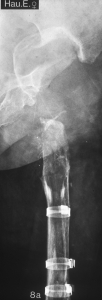

Abb. 8

Der

Probierschaft wird eingebracht. |